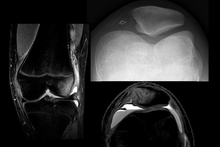

| Radiograph of a patient with patellar dislocation. Normally the patella projects over the distal femur. | |

Patellar dislocation is an injury of the knee, typically caused by a direct blow or a sudden twist of the leg.[1] It occurs when the patella (kneecap) slips out of its normal position in the patellofemoral groove, and generally causes intense pain with swelling of the knee.[1] Open or arthroscopic surgery may be used to repair damage, but are typically avoided since rates of re-injury, knee function, and patients' opinions do not differ much from conservative treatment.[2][3][4]